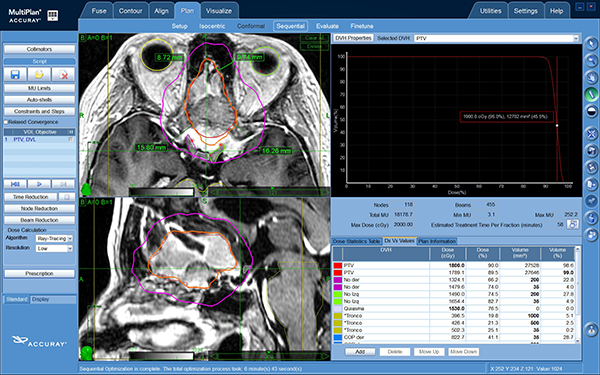

El paciente atiende al proceso de simulación, el cual consiste en configurar una máscara termoplástica que ayudará a limitar el movimiento de la cabeza durante el tratamiento, se adquiere un TAC sin contraste o con contraste cuando se es necesario de la totalidad de la cabeza incluyendo hasta la segunda o tercera vértebra cervical abarcando la totalidad de la mandíbula. Posteriormente, se adquieren las secuencias necesarias de resonancia magnética 1.5 Tesla (General Electric, Massachusetts, USA) en secuencias de T1 MPR Gadolinio y T2 FIESTA que es el equivalente al CISS cuando se es necesario, el paciente es dado de alta del centro de imágenes y convocado para tratamiento usualmente en 48 a 72 horas después. Las imágenes son transferidas a la consola de MultiPlan™ (Accuray, Sunnyvale California), y son fusionadas, la lesión o target (GTV Gross Tumor Volume) es contorneado al igual que todas las estructuras en riesgo que involucran cerebro, tronco encefálico, ojos, vía óptica y paladar duro para evitar haces de radiación entrando por la boca. Utilizando la modalidad de 6D Skull para tracking se efectúa el cálculo de dosis de forma inversa -Inverse Planning-.

Figura 3: Imagen de Multiplan en Cyberknife en modalidad de radiocirugía fraccionado con la curva anaranjada interna que representa la dosis de prescripción de 18 Gy y la curva más externa en rosado representa la mitad de la dosis de prescripción (9 Gy).